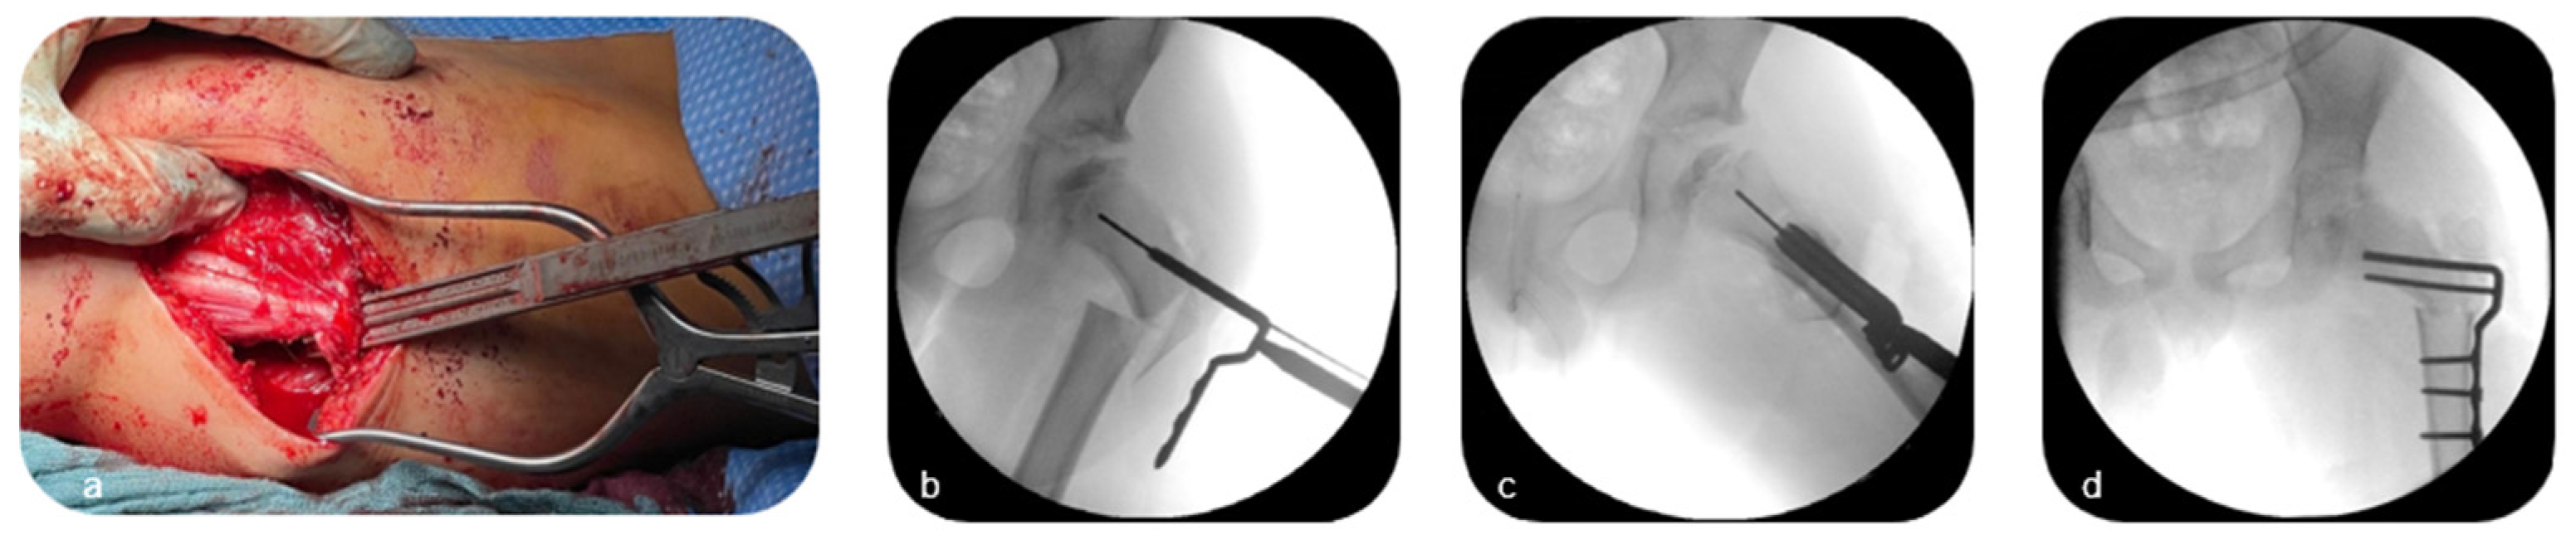

The patient was initially placed in lateral decubitus position. A standard lateral approach to the proximal femur was performed, and the fascia lata was split to visualize the posterior aspect of the greater trochanter (Figure 2a). The latter was than separated from the proximal femur in compound with the attachment of the gluteus medius and vastus lateralis muscles through a vertical osteotomy with an oscillating saw (Figure 2b,c) before it was distalized under abduction of the hip. Excessive medial penetration of the proximal femur with the saw and osteotome, respectively, was avoided to prevent the risk of injury to the medial femoral circumflex artery.

Figure 2. Lateral approach to the proximal femur with a fascia lata split (a) and vertical osteotomy at the base of the greater trochanter (b,c) (Patient 3; see Table 1).